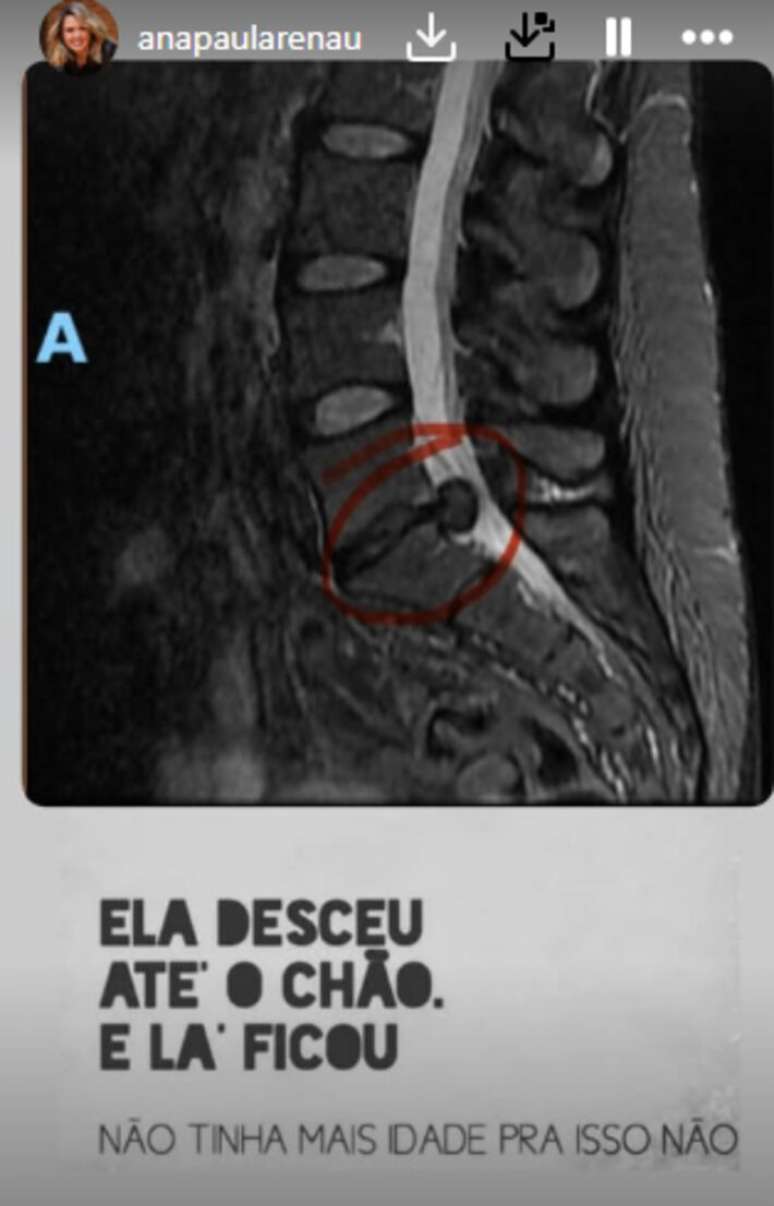

A internação de Ana Paula foi motivada por uma hérnia de disco de grandes proporções. Segundo a ex-BBB, os médicos ficaram alarmados com o tamanho da hérnia após realizarem uma ressonância magnética. Ana disse que a condição estava comprimindo estruturas nervosas, o que levou à decisão de realizar uma cirurgia de emergência para evitar danos permanentes.

Ana Paula Renault mostra sua hérnia de disco:

Ana Paula Renault mostra sua hérnia de disco